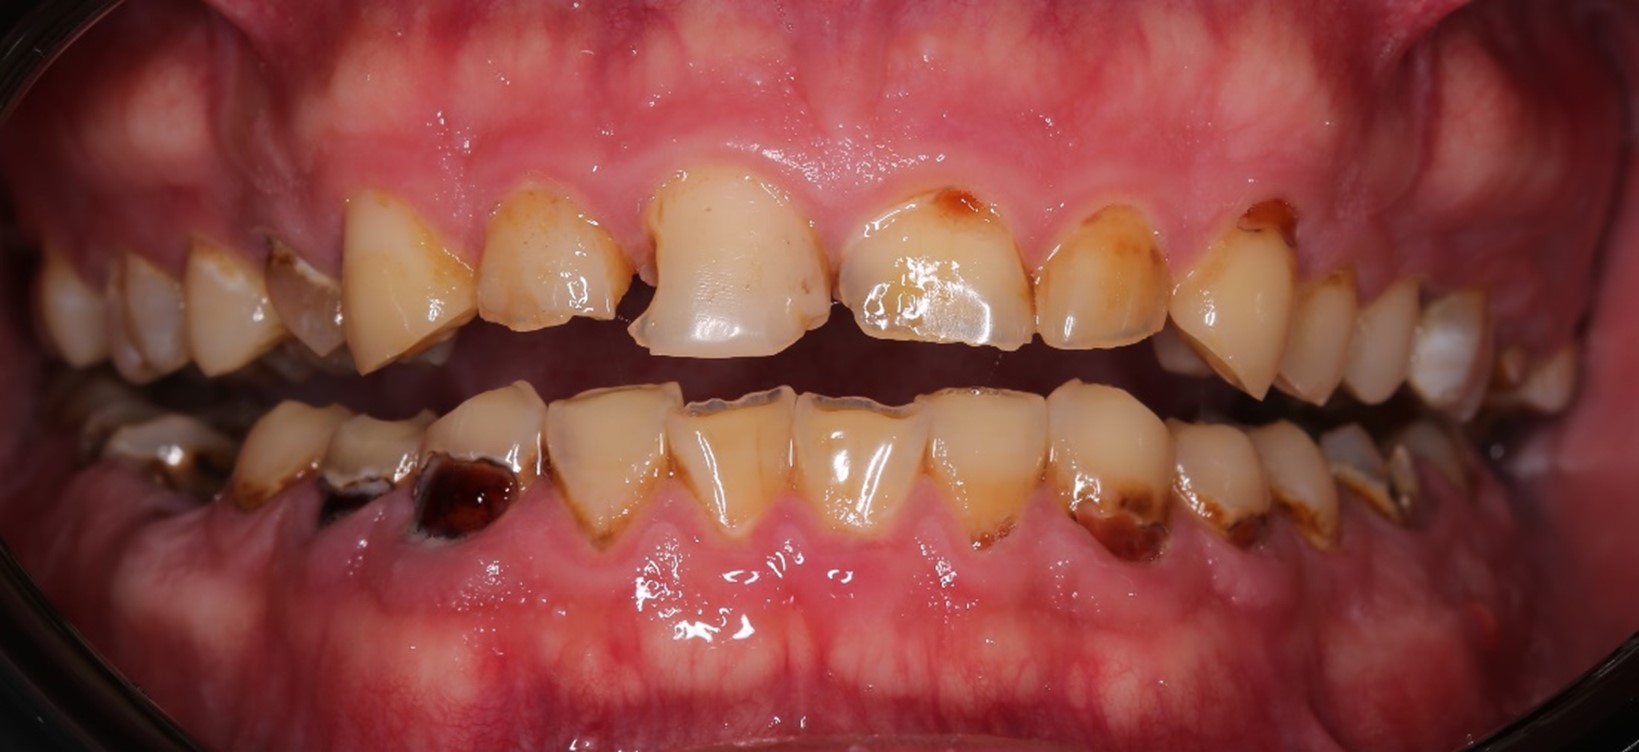

Напоминаю: он пришёл к нам вот в таком состоянии:

Жалобы были не только на внешний вид зубов, но ещё и на проблемы с дыханием и приёмом пищи. Общаться с людьми было тоже некомфортно.

Во-первых, нам нужно было сохранить как можно больше живых зубов при условии, что ни одного целого не было: везде либо вторичный кариес под пломбами, либо сколы, либо стёртые зубы, либо сильно разрушенные. А на фронтальной группе — всё это сразу.

В жевательном отделе зубов практически нет. На зубах с первого по пятый появились небольшие фасетки стираний, которые означают, что прикус зафиксирован именно на них. Если они настолько отчётливые, как у Ивана, это значит, что зубы начинают стираться, и высота нижнего отдела лица уменьшается. Значит, придётся повышать прикус, чтобы вернуть височно-нижнечелюстной сустав и зубы в первоначальную здоровую позицию. Это будет моей задачей.